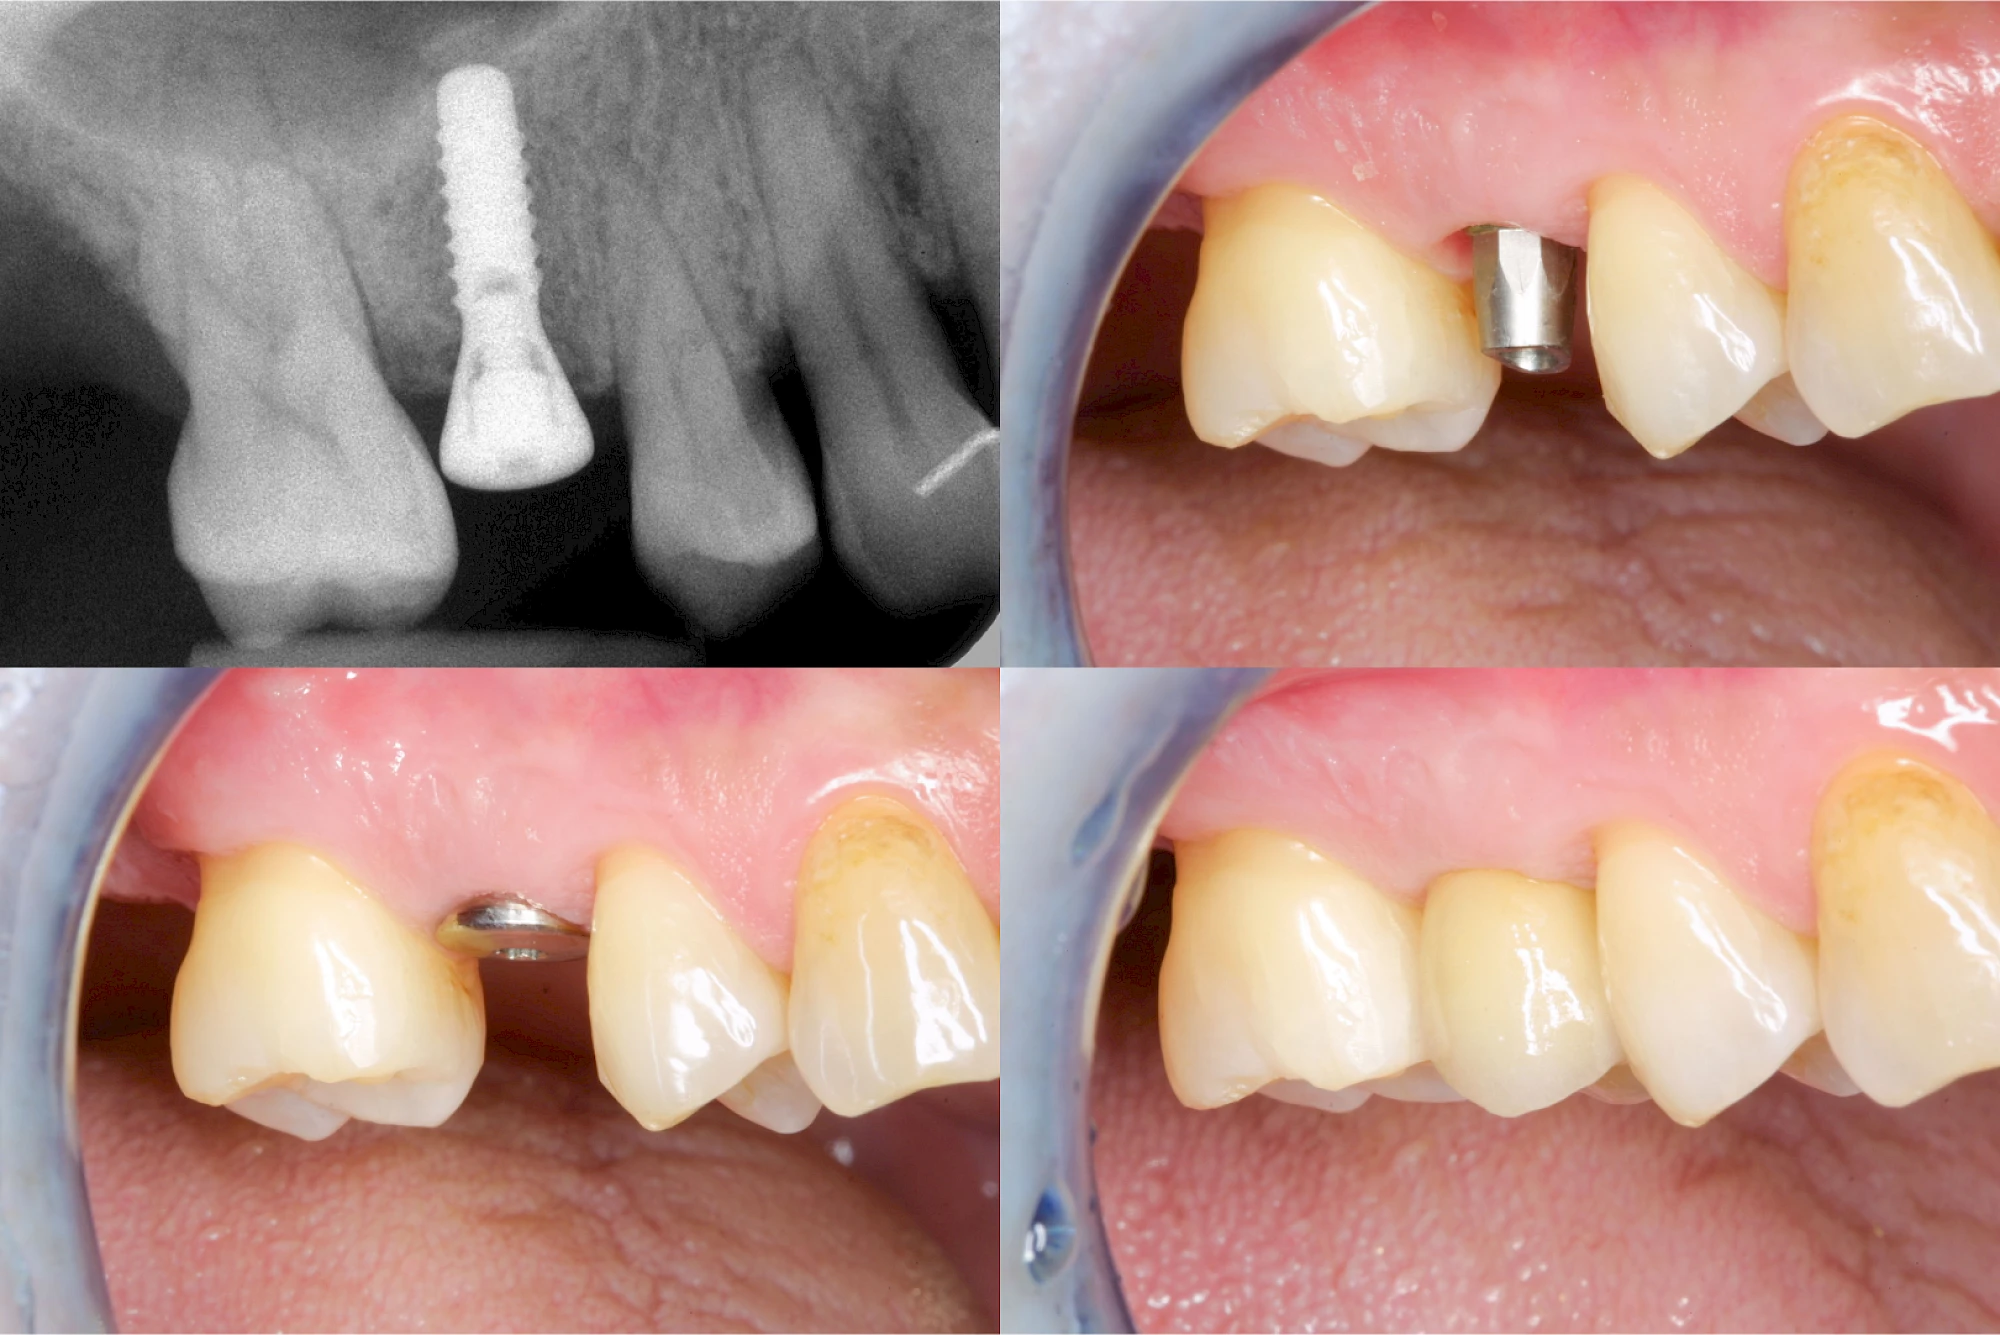

Implantate: Bestandteile

Implantate sind künstliche Zahnwurzeln. Nach einer gewissen Einheilzeit im Knochen (meist 3-6 Monate) erfolgt über einen separaten Aufbau (Abutment) die Befestigung einer Krone bzw. Brücke oder Zahnprothese.

In seltenen Fällen sind Implantate samt Aufbau aus einem Stück gefertigt. Auch gibt es Situationen, die ein Früh- oder sogar eine Sofortbelastung erlauben – dann kann die Einheilzeit der Implantate in den Knochen verkürzt oder sogar gänzlich darauf verzichtet werden.

Implantate: Kronen & Brücken

Fehlen einzelne Zähne und die Nachbarzähne sind unbeschadet oder gut zahnärztlich versorgt, werden immer häufiger Implantate gewählt, um die Lücken zu schließen. Auch bei größeren oder verteilten Lücken, wenn keine herausnehmbare Prothese gewünscht ist, werden Implantate für Kronen- bzw. Brückenversorgungen gesetzt. In Einzelfällen entscheiden sich sogar zahnlose Patienten für eine festsitzende Versorgung auf Implantaten.

Varianten zur Verankerung von festsitzendem Zahnersatz auf Implantaten